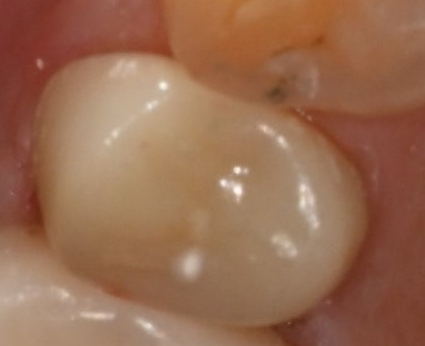

The final step is a strong finish with a zirconia crown

Once the root canal treatment is complete, the final step is

to finish with a zirconia crown.

Zirconia is highly durable,

long-lasting, resistant to breaking,

and has a natural color,

so it is a material that fits molars very well.

Once the crown is placed like this,

even when a molar breaks,

its function can be restored almost to how it was originally.